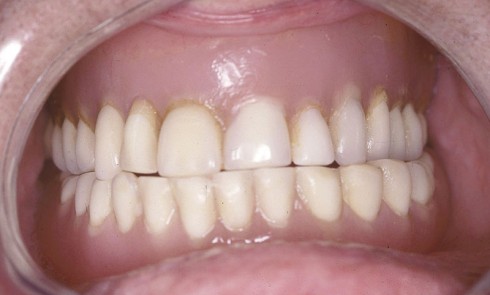

Article réservé à nos abonnés La prothèse composite dans la gestion esthétique et biomécanique d’un édentement unilatéral de grande étendue

La réhabilitation des édentements terminaux unilatéraux de grande étendue par prothèse amovible partielle métallique (PAPIM) conventionnelle pose plusieurs problèmes essentiellement...